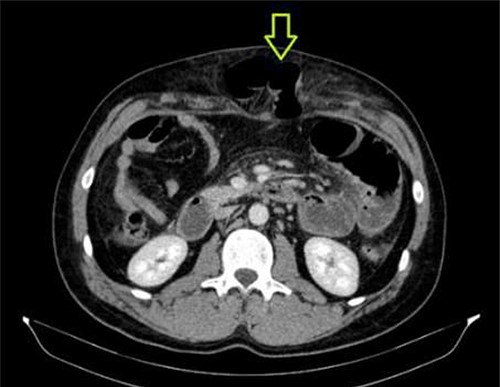

A 41-year-old man presented to the emergency room soon after falling from his motorcycle and hitting his handlebars in the epigastric region. The patient’s vital signs and initial laboratory studies were normal. Physical examination showed a soft tissue bulge in the epigastric region with superficial ecchymosis and tenderness to palpation. The swelling was obvious on standing and less evident when lying supine (Fig. 1). Focused Assessment with Sonography for Trauma (FAST) performed in the emergency room did not show free fluid in the abdominal cavity. Computed tomography (CT) scan showed intestinal loops protruding through a defect in the abdominal wall into the subcutaneous space (Figs 2 and 3). Therefore, a surgical approach for handlebar hernia treatment was decided on the first day of hospitalization. A defect throughout the entire abdominal wall, including the fascia, muscular layers and peritoneum, with bowel protruding into the subcutaneous space, was observed during surgery (Fig. 4). There was no blood or fecal contamination in the area immediately surrounding the lesion, and exploration of the bowel loops did not reveal signs of intra-abdominal injury. Based on this, hernia repair was performed with prosthetic material (Fig. 5). As there was no evidence of intra-abdominal injury, local wound exploration provided the best anatomic layered repair with subsequent minimal residual defect and improved long-term cosmesis. The defect was repaired in layers, and the patient postoperative course was uneventful.

CT abdomen showing abdominal wall hernia containing a loop of small intestine (green arrow).